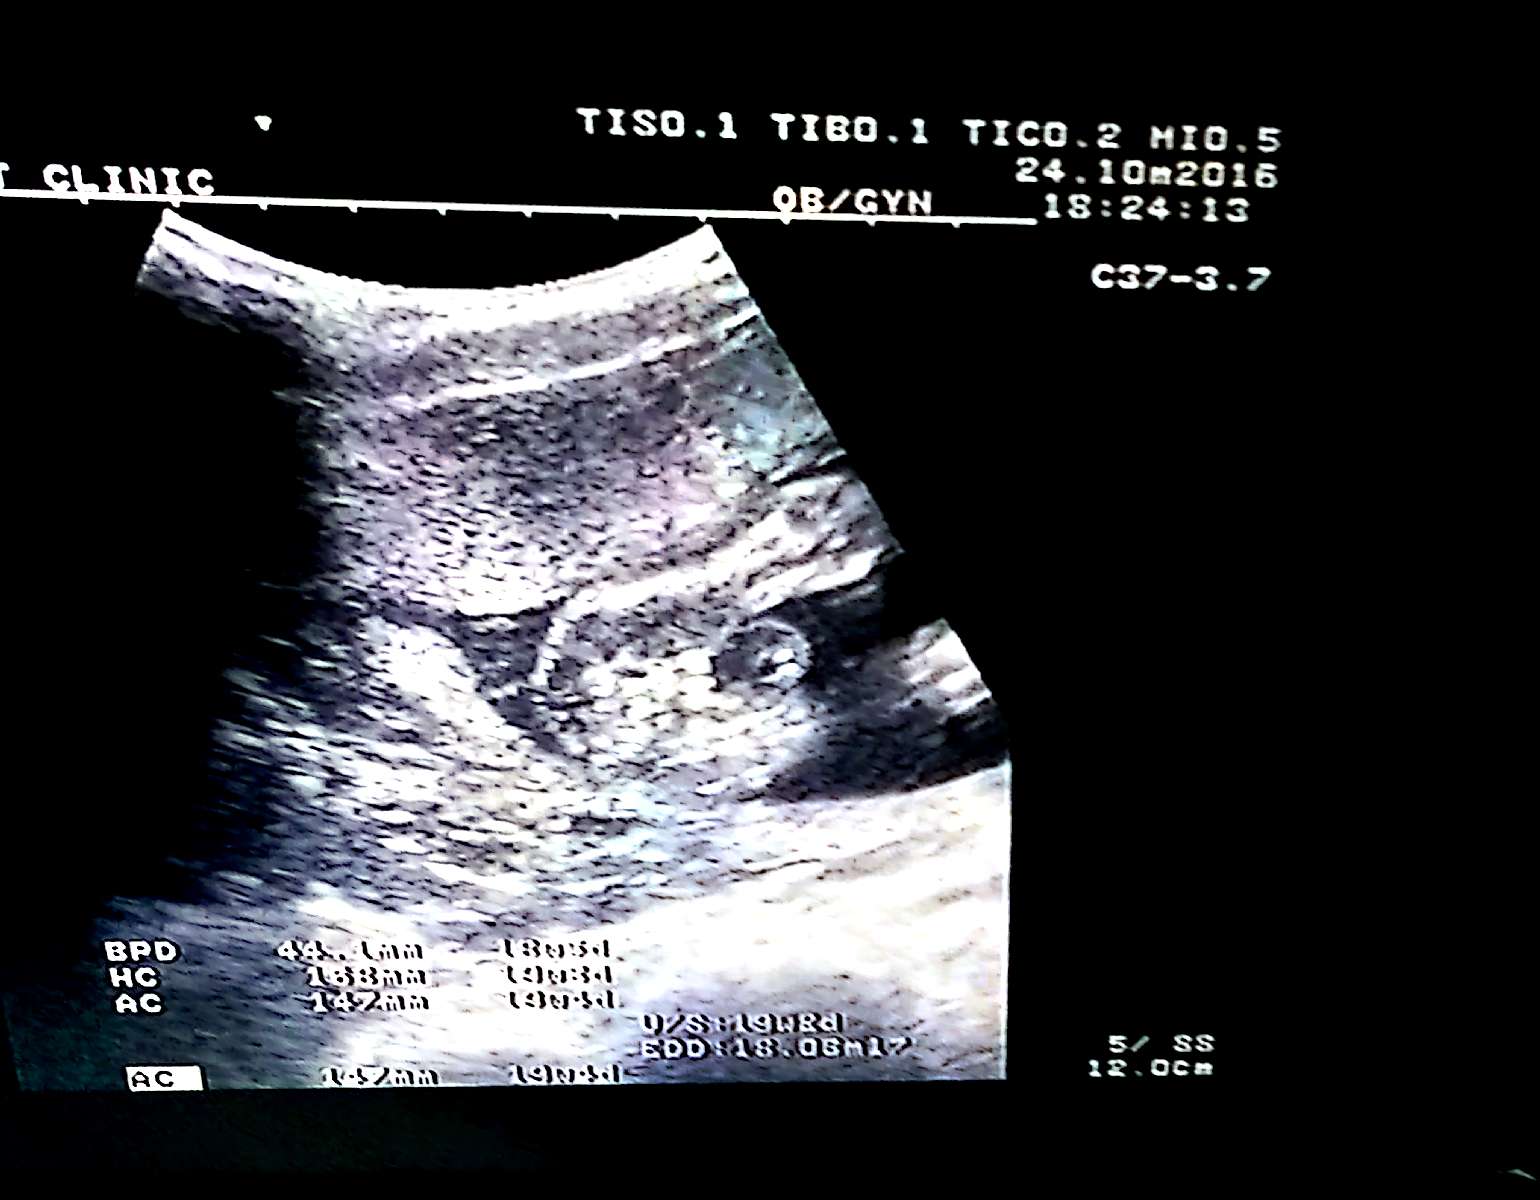

รบกวนช่วยดูเพศลูกให้หน่อยครับ